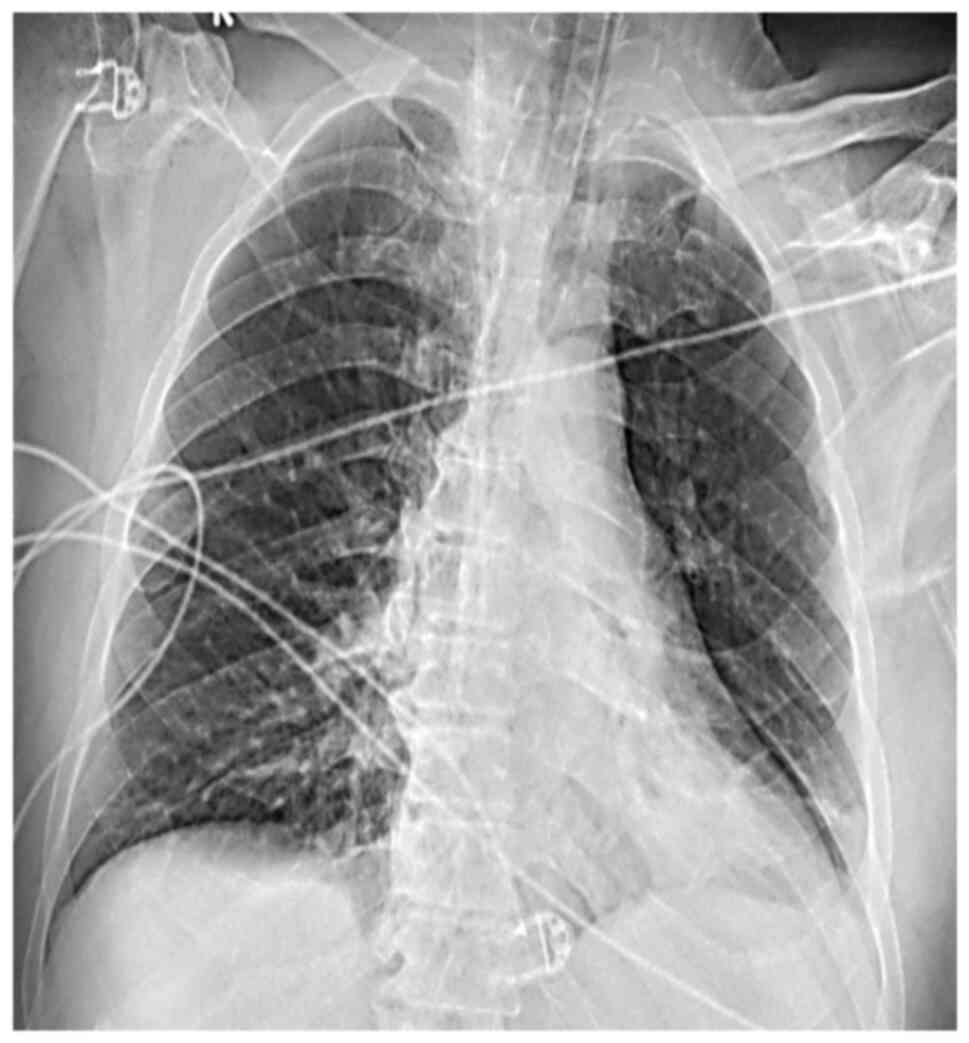

Therapy was continued only with acyclovir at 10 mg/kg three times. The CSF culture tested negative. His chest X-ray was negative (Fig. 1). The blood test results of the patient are presented in Table I.

Figure 1

X-ray image of the patient upon admission.